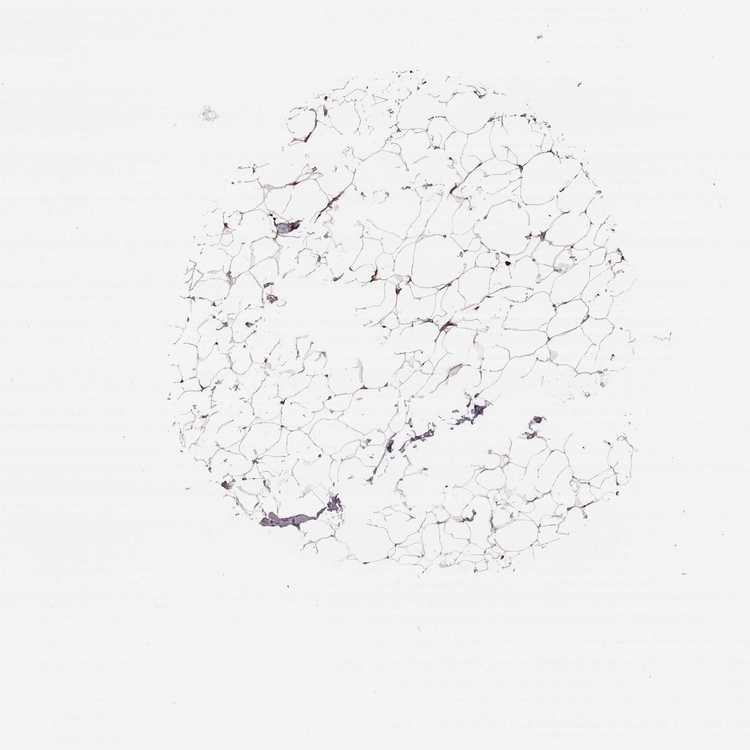

BREAST - Antibody stainingi

Antibody staining in the annotated cell types in the current human tissue is reported as not detected, low, medium, or high, based on conventional immunohistochemistry profiling in selected tissues. This score is based on the combination of the staining intensity and fraction of stained cells.

Each image is clickable and will lead to virtual microscopy that enables deeper exploration of all samples and also displays staining intensity scores, fraction scores and subcellular localization as well as patient and tissue information for each sample.

Antibody HPA065254

Adipocytes Not detected

Glandular cells High

Myoepithelial cells High